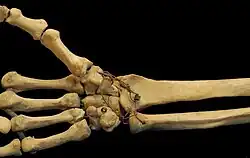

Bones of a human wrist. In this photo both the free position and the saddle shape of the first CMC joint and the proximal transverse palmar arch are clearly visible.